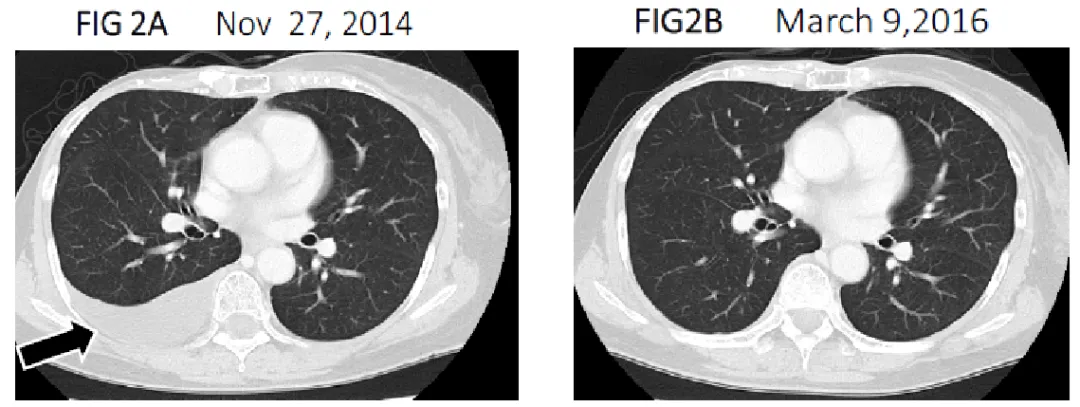

《英国癌症研究杂志》报道了一则HER2阳性转移性乳腺癌案例:46岁女性患者术后8年因肿瘤进展、严重副作用及淋巴细胞耗竭,入组接受NK细胞+αβT细胞+联合治疗。

结果显示:入组时胸部CT显示其右侧胸腔存在积液;治疗1年后,胸部CT证实恶性胸腔积液完全消失(详见下图),肿瘤标志物恢复正常,免疫功能(CD4/CD8比例)稳定,体能状态恢复至病前水平。后续10年持续接受间歇性αβT细胞治疗联合化疗,截至2021年,患者术后已存活25年且健康状况良好,成为目前文献报道中该疗法下生存期最长的案例。

▲图源“BJCR”,版权归原作者所有,如无意中侵犯了知识产权,请联系我们删除